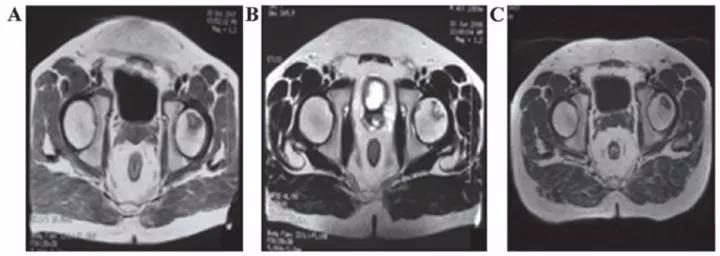

? 股骨頭壞死

間充質(zhì)干細(xì)胞移植治療人體股骨頭壞死在國(guó)外已有報(bào)道。法國(guó)科學(xué)家移植治療116例股骨頭壞死患者效果顯著,其中87.3%的患者髖關(guān)節(jié)疼痛緩解;78.4%的患者關(guān)節(jié)功能改善;80%的患者行走間距延長(zhǎng)。

吉林一位許姓小伙在一次攀巖活動(dòng)中從高處摔下來(lái),送到醫(yī)院檢查,雙側(cè)股骨頭已壞死變形。按照常規(guī)治療方法,應(yīng)行人工關(guān)節(jié)置換手術(shù)??墒侨嗽旃晒穷^的壽命一般在10-15年,小許才27歲,一輩子需要不停地更換人工關(guān)節(jié)。

沈陽(yáng)463醫(yī)院的楊曉鳳主任將間充質(zhì)干細(xì)胞經(jīng)過(guò)技術(shù)處理后注入小許的股骨頭,兩周后小許就可以下地行走了。10個(gè)月后,小許來(lái)醫(yī)院復(fù)查,他的股骨頭周?chē)验L(zhǎng)出豐富的血管,表明移植的間充質(zhì)干細(xì)胞促使壞死變性的股骨頭修復(fù)新生。

表8 劉穎、谷涌泉應(yīng)用臍帶MSC治療股骨頭壞死的臨床研究結(jié)果

吉林省組織工程重點(diǎn)實(shí)驗(yàn)室劉穎教授 、首都醫(yī)科大學(xué)宣武醫(yī)院谷涌泉主任等,對(duì)9位骨循環(huán)協(xié)會(huì)評(píng)級(jí)為II-IIIa級(jí)的股骨頭壞死患者經(jīng)大腿動(dòng)脈輸注臍帶間充質(zhì)干細(xì)胞后,患者的紅細(xì)胞、血小板、血氧轉(zhuǎn)運(yùn)指數(shù)明顯改善。MRI檢測(cè)顯示24個(gè)月后股骨頭壞死區(qū)域體積顯著減少。